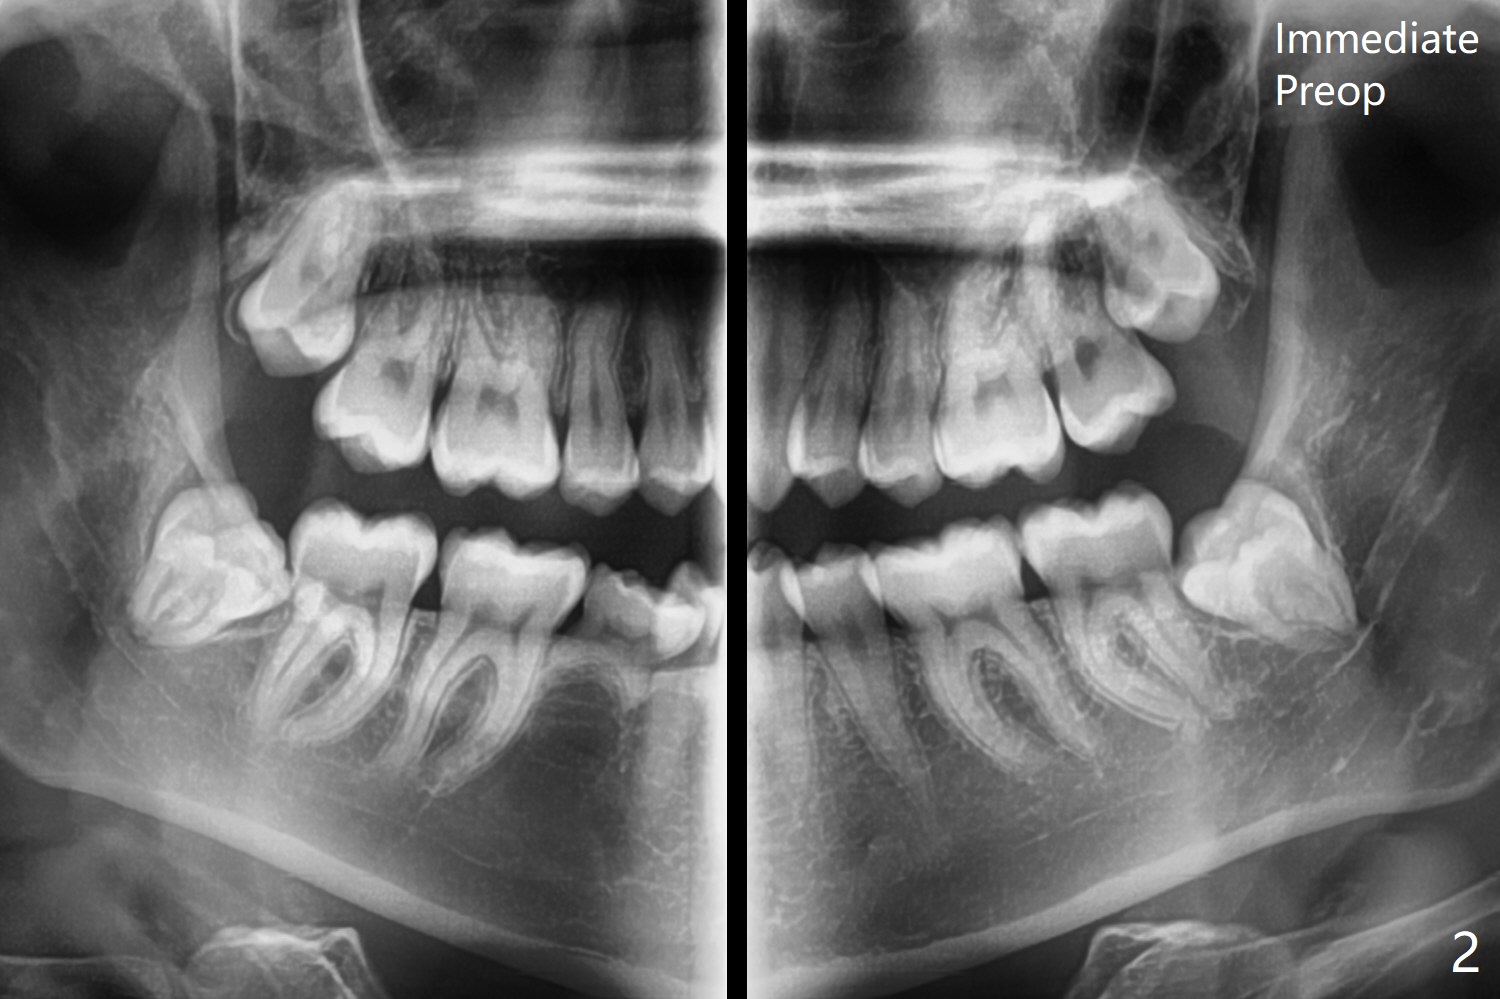

A 21-year-old nervous woman wants to have 4 of the 3rd molars extracted (Fig.1). To prevent dry socket, place collagen plug at #17 and 32. Take panoramic 4 Bitewings postop and preferably preop, since Fig.1 was taken on January 1, 2018 and #17 and 32 are close to the Inferior Alveolar Canals. In fact Osteogen plug is placed at #16 and 17 due to apparently severe bony defect affecting the neighboring teeth, while Collagen plug at #32.